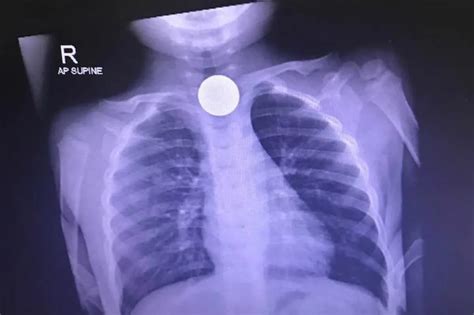

Nakalunok Ng Buto Ng Manok

Batang nakalunok ng barya, nakaligtas | ABS-CBN News

Buto Mg Manok SA Lalamunan

Lalaki Namatay Matapos Kumain Ng Buto Ng Manok